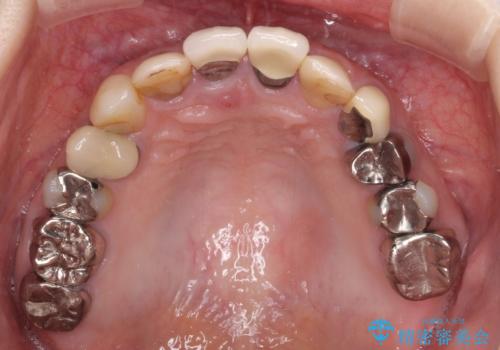

- 以前から前歯の根が折れていると言われていたものの放置しており、いよいよ痛みが気になってきたとのことで来院された患者様です。

検査の結果、右前歯の歯根が縦に破折していることが分かりました。

破折している歯は抜歯をし、歯肉が窪んでしまうので、傷口の治りを待って、歯肉移植を行うこととしました。

歯肉移植終了後、オールセラミックブリッジにて補綴することとしました。